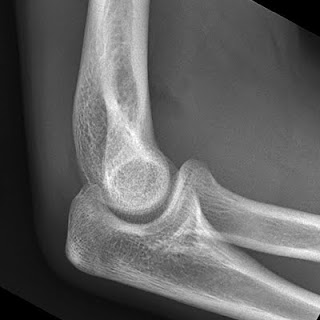

یکی از این موارد مشکوک بودن به شکستگی اندام ها در کودکان و نوجوانان است.

چون در این سن استخوان ها هنوز در حال رشد هستند خطوط اپی فیزیال از انتهای اندام ها جدا به نظر می رسند و این می تواند باعث تشخیص نادرست پزشک شود.در چنین موردی باید یک عکس دیگر از اندام مقابل گرفته شود.

خودم چند مورد دیده ام که مثلا آرنج بچه ای ضربه خورده است و پس از عکسبرداری پزشک درتشخیص شکستگی دچار اشتباه شده است و دستور گچ کرفتن داده است.در صورتی که شکستگی در کار نبوده است.لذا در این گونه موارد عکسبرداری مقایسه ای واقعا به کار می آید.

یادمان باشد هر گردی گردو نیست و هر خط شکستگی ، شکستگی نیست.